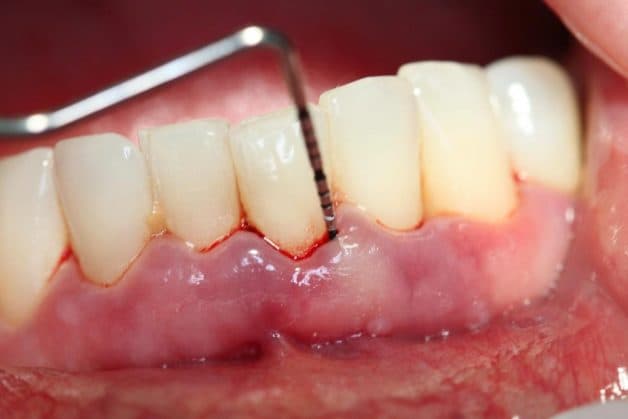

Phần lợi bị sưng phồng và chảy máu